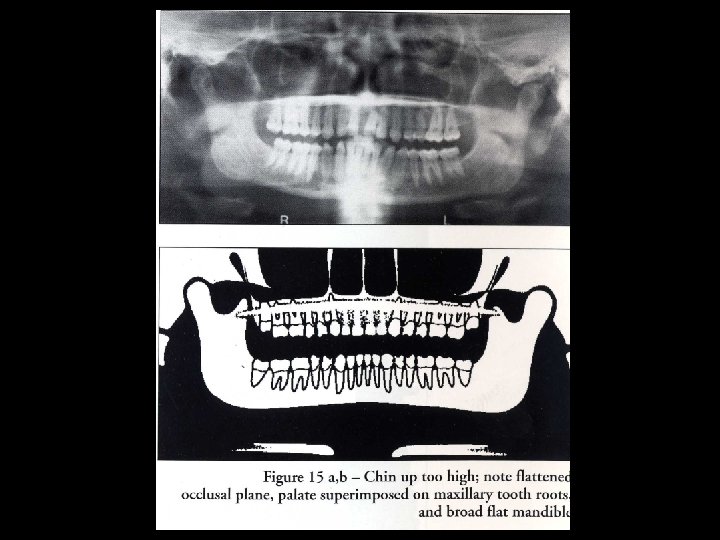

Ghost image